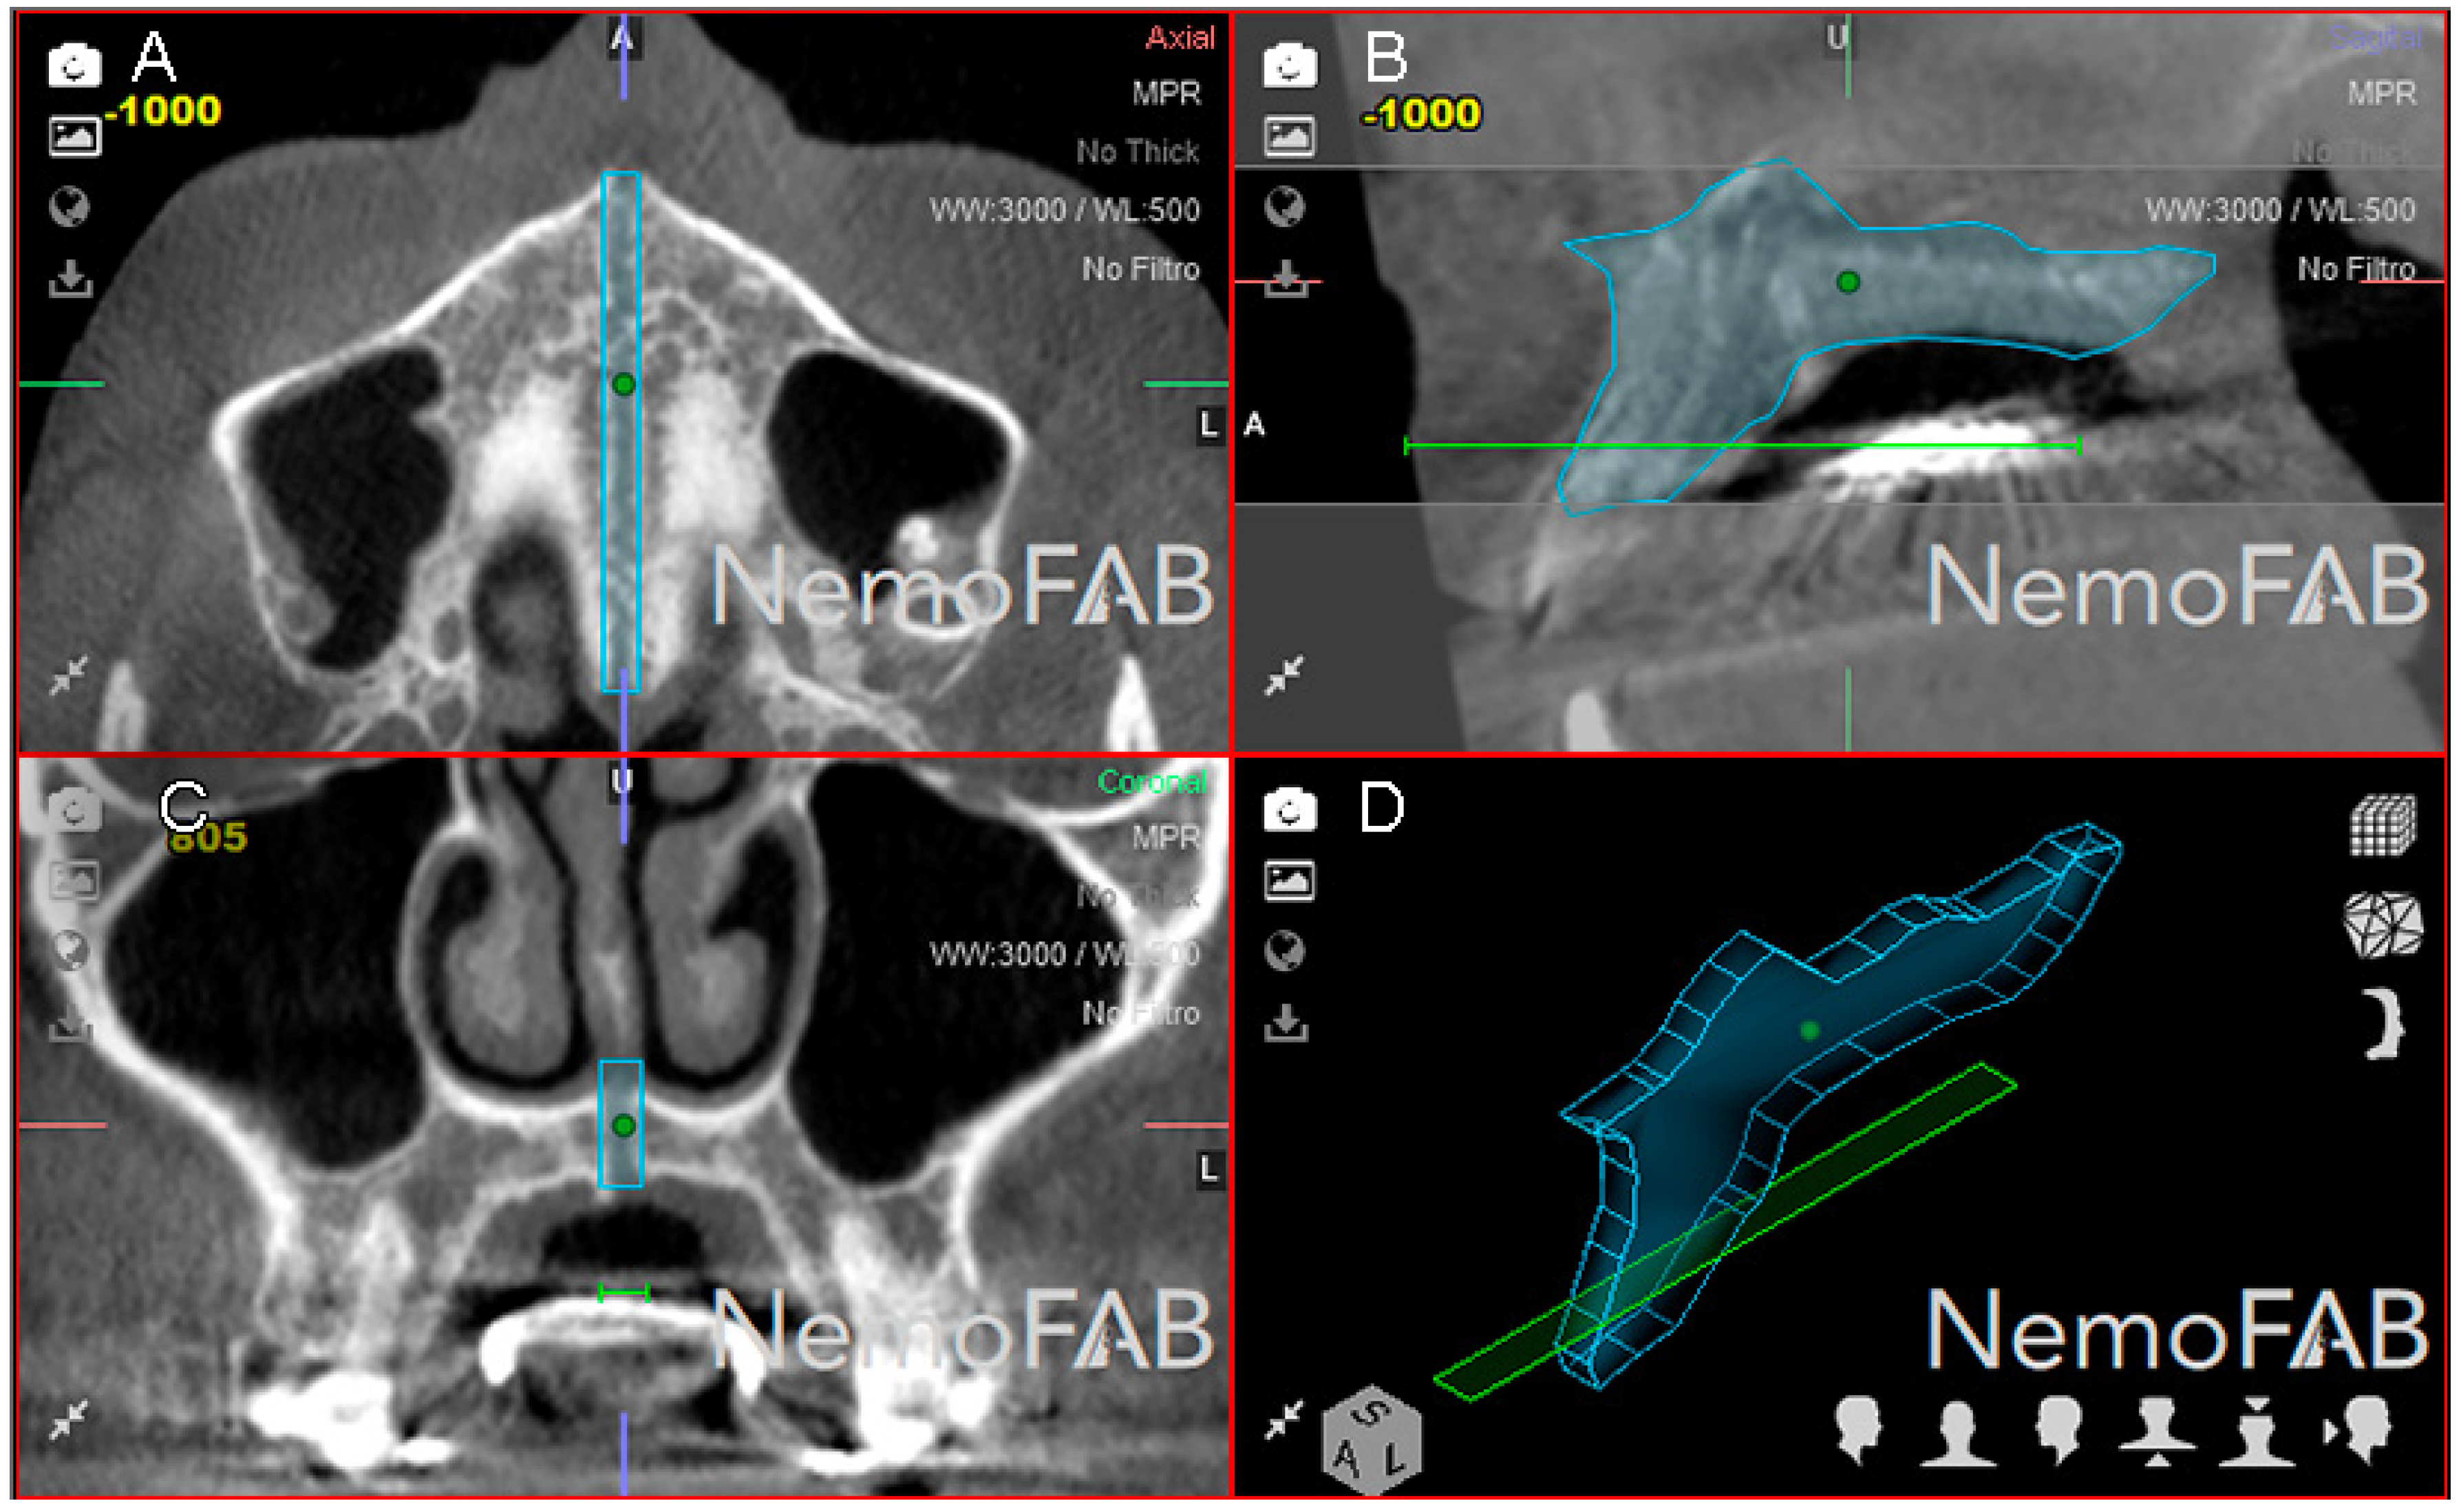

Afterwards, a reference point (seed point) was placed inside the selected and isolated geometric prism of the expanded palatine suture at the transversal (Figure 4A), sagittal (Figure 4B) and coronal (Figure 4C) plane and the three-dimensional reconstruction (Figure 4D). This was to ensure a tissue density with a tolerance range of 500 Hounsfield units (HU), corresponding to the soft tissue density formed after the palatine suture expansion was performed according to the study of Buzatu et al. who measured the density of the palatal suture after RME procedures ranging between 128.56 HU (middle segment in women) and 398.07 HU (posterior segment in men) [27]. In the present study, a 500 HU tolerance range was established to ensure that the entire palatal suture expansion was registered inside the previously defined geometric prism.

Figure 4.

(A) Boundaries of the palatine suture (blue line) after the RME procedure through McNamara appliance with the seed point inside, at transversal plane, (B) sagittal plane, (C) coronal plane and (D) at three-dimensional reconstruction.